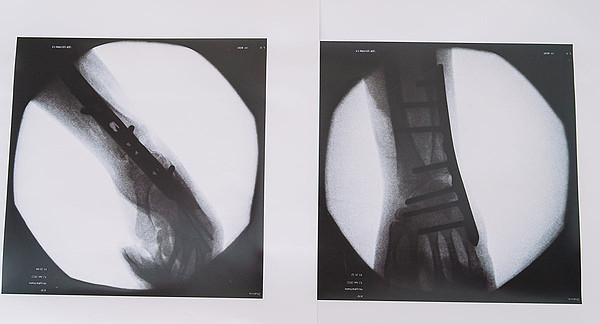

2401-1Фото-8

2401-1.